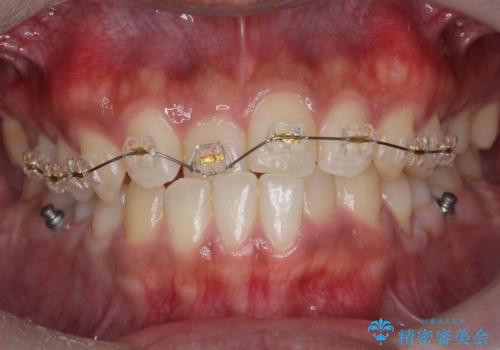

骨格性の受け口の矯正 部分ワイヤーで上の前歯を前に、 マウスピースで下の前歯を後ろに。

- 受け口を主訴に来院。

前歯のかみ合わせが逆になり上の前歯が奥に入っていました。

骨格性の受け口だったため、矯正用のミニスクリューを用いて、下の前歯をしっかり内側に入れました。

前歯を前に乗り越えさせるのは、ワイヤー矯正が一番早く歯に負担がかかりにくいです。

また、下顎はミニスクリューからマウスピースにゴムをかけて、下の歯並びが前に出ないようにして並べています。